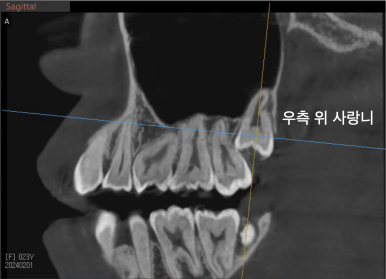

우측 위의 사랑니는 앞쪽 치아에 완전히 걸려있었고 (좌측 사진), 우측 아래의 사랑니는 신경관과 딱 닿아있었네요.. (우측 사진)